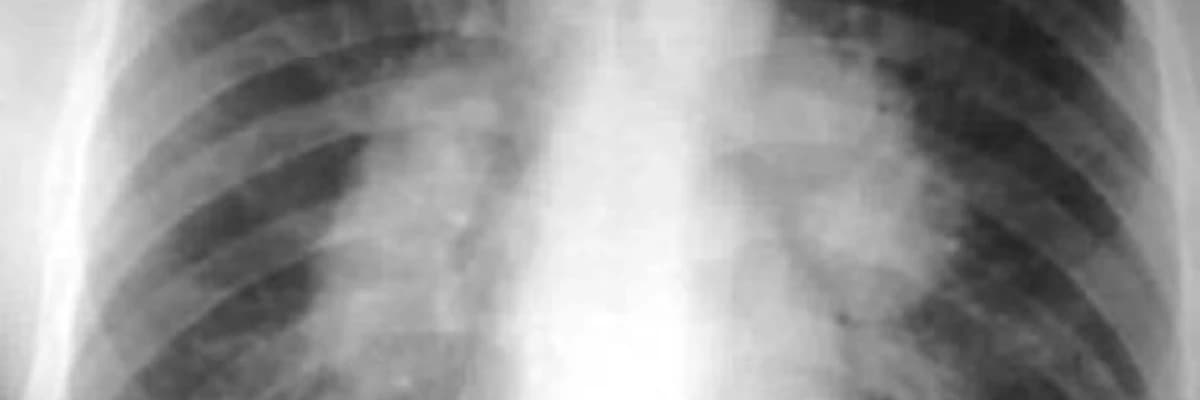

Sarkoidoz, bədənin müxtəlif hissələrində, xüsusən də ağciyərlərdə iltihabi qranulomların (kiçik, yuvarlaq şişlərin) yaranması ilə xarakterizə olunan bir xəstəlikdir. Çox hallarda, sarkoidoz öz-özünə düzələn və ya hafif simptomlarla gələn bir vəziyyətdir və adətən steroidlər kimi dərmanlarla müalicə edilir. Lakin, ağır və ya davamlı hallarda cərrahi müdaxilə tələb edilə bilər.